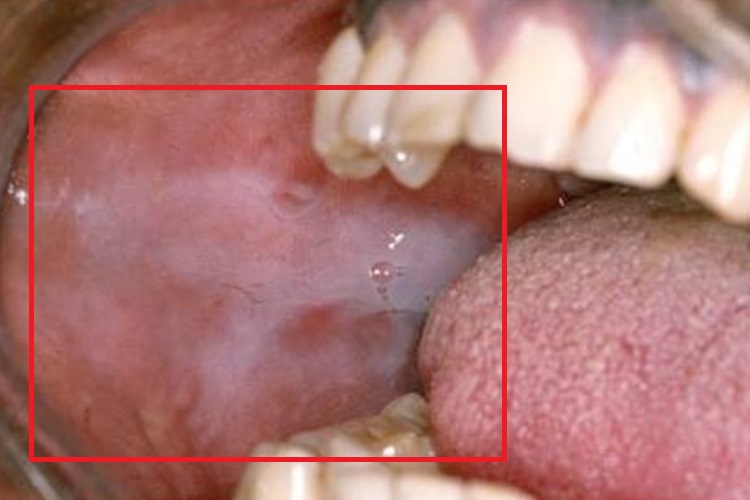

药物过敏性口炎:疾病初起时,口腔两侧颊黏膜有烧灼感,明显充血、发红且水肿,可出现红斑、水疱,但水疱很快破溃形成糜烂或溃疡。病变面积较大,外形不规则,表面有较多渗出物,还会形成灰黄色或灰白色假膜。